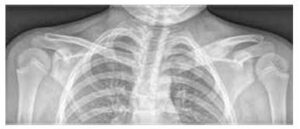

Obrázek č. 2

Porovnání distribuce kostních ložisek na MR dětí s CRMO a se septickou osteomyelitidou (podle Schnabel et al., 2016)